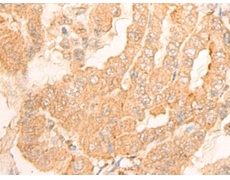

ELISA, IHC |

IHC Positive control: |

Human thyroid cancer; |

IHC Recommended dilution: |

25-100 |